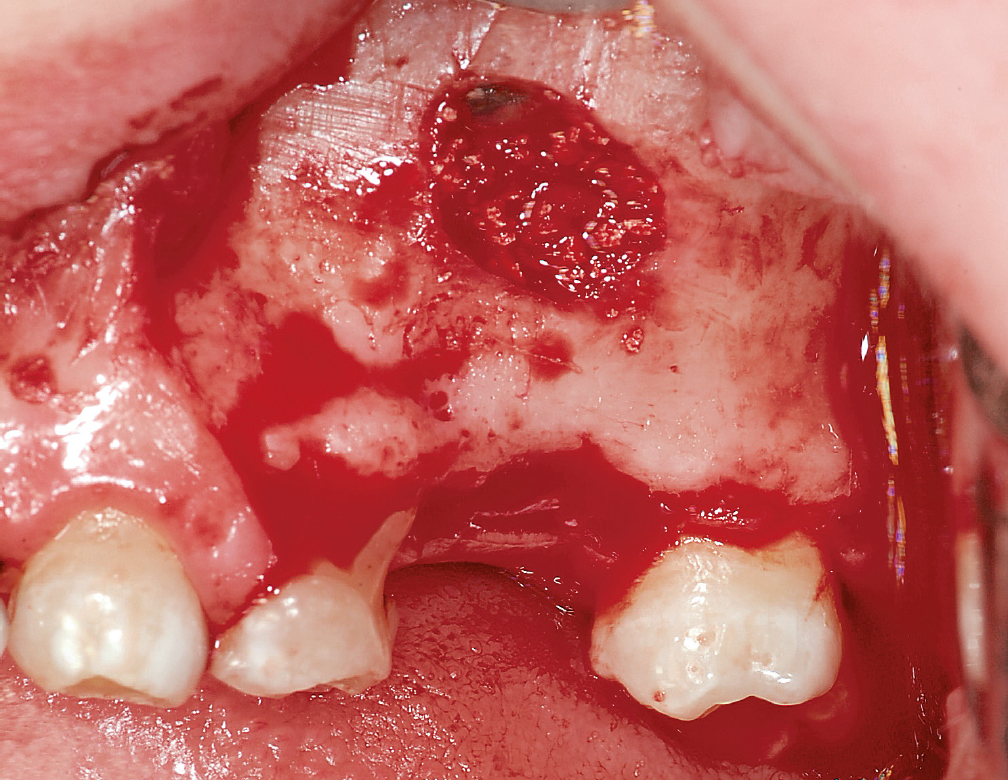

Im Rahmen der „Consensus Reports“ 2015 der European Association for Osseointegration (EAO) wurde kein ausreichender Nutzen für die präoperative Antibiotikaprophylaxe im Fall einfacher Implantationen bei gesunden Patienten gesehen. Insbesondere im Hinblick auf das Problem der Antibiotikaresistenzentwicklung und das Vorkommen von unerwünschten Nebenwirkungen wird daher die Empfehlung zur perioperativen Antibiotikaprophylaxe kritisch betrachtet. Für kompliziertere Fälle konnte hingegen ein Nutzen der Prophylaxe zumindest nicht ausgeschlossen werden27,28 (Abb. 1). Eine prolongierte Antibiose über 3 bis 5 Tage kann bei Augmentationen erwogen werden, denn es hat sich gezeigt, dass unabhängig von der Art der Knochenentnahme eine bakterielle Kontamination des Augmentationsmaterials nahezu unvermeidbar ist (Abb. 2). Auch bei der Verwendung von Knochenersatzmaterial sollte eine prolongierte Antibiose über einige Tage verordnet werden, da es sich primär um ein Fremdmaterial handelt (Abb. 3).

Abb. 2 Die bakterielle Kontamination von Knochenaugmentaten kann bei intraoralen Eingriffen kaum vermieden werden. Ein ausreichender perioperativer Antibiotikaspiegel ist daher zur Infektionsprophylaxe ratsam (Bild aus23).